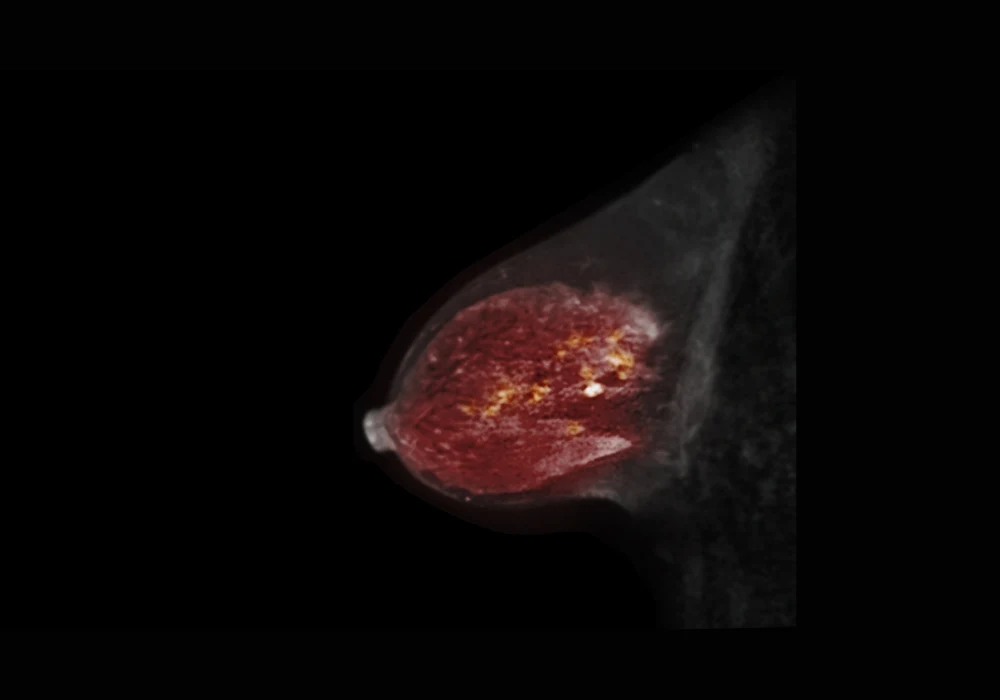

Magnetic resonance imaging (MRI) plays a vital role in breast cancer screening by providing highly detailed anatomical and physiological images without exposing patients to ionising radiation. Despite its clinical value, breast MRI is underused in screening due to long scan times, high costs and reduced patient throughput. Traditional MRI protocols are lengthy, often including multiple imaging sequences that add complexity without necessarily improving diagnostic outcomes. Abbreviated breast MRI (AB-MRI), which excludes non-essential sequences, has been proposed as a faster alternative, but its adoption has been slow. A new approach using artificial intelligence offers a solution by allowing real-time decisions on whether to complete the full MRI protocol or conclude early with AB-MRI, potentially transforming the way breast MRI is performed.

In standard clinical practice, radiologists decide on the MRI protocol in advance. This means all patients undergo a fixed series of imaging sequences, regardless of their individual risk profile or the imaging findings that emerge during the scan. The AI-directed scanning model offers a more adaptive alternative. This method uses an AI triage tool to analyse dynamic contrast-enhanced (DCE) images early in the scan, generating a suspicion score. Based on this score, the system decides in real time whether to proceed with the full set of sequences or stop the scan at the abbreviated protocol stage.

These findings suggest that AI triage safely identifies which patients require full imaging and which do not, reducing unnecessary scanning without compromising patient care. The approach is especially effective because cancers are typically identified on DCE images, while the additional sequences in full MRI are mainly used for further characterisation. By using DCE images as the basis for triage, AI enables focused imaging that preserves diagnostic integrity.